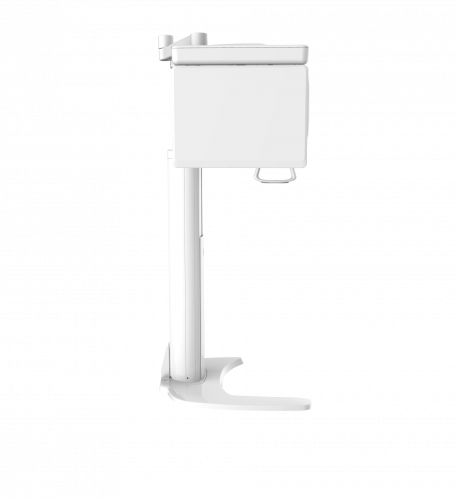

| TYPE | TOP VIEW | FRONT VIEW |

|---|---|---|

|

PaX-i (Pano) |

|

|

|

PaX-i SC (Pano/Scan Ceph) |

|

|